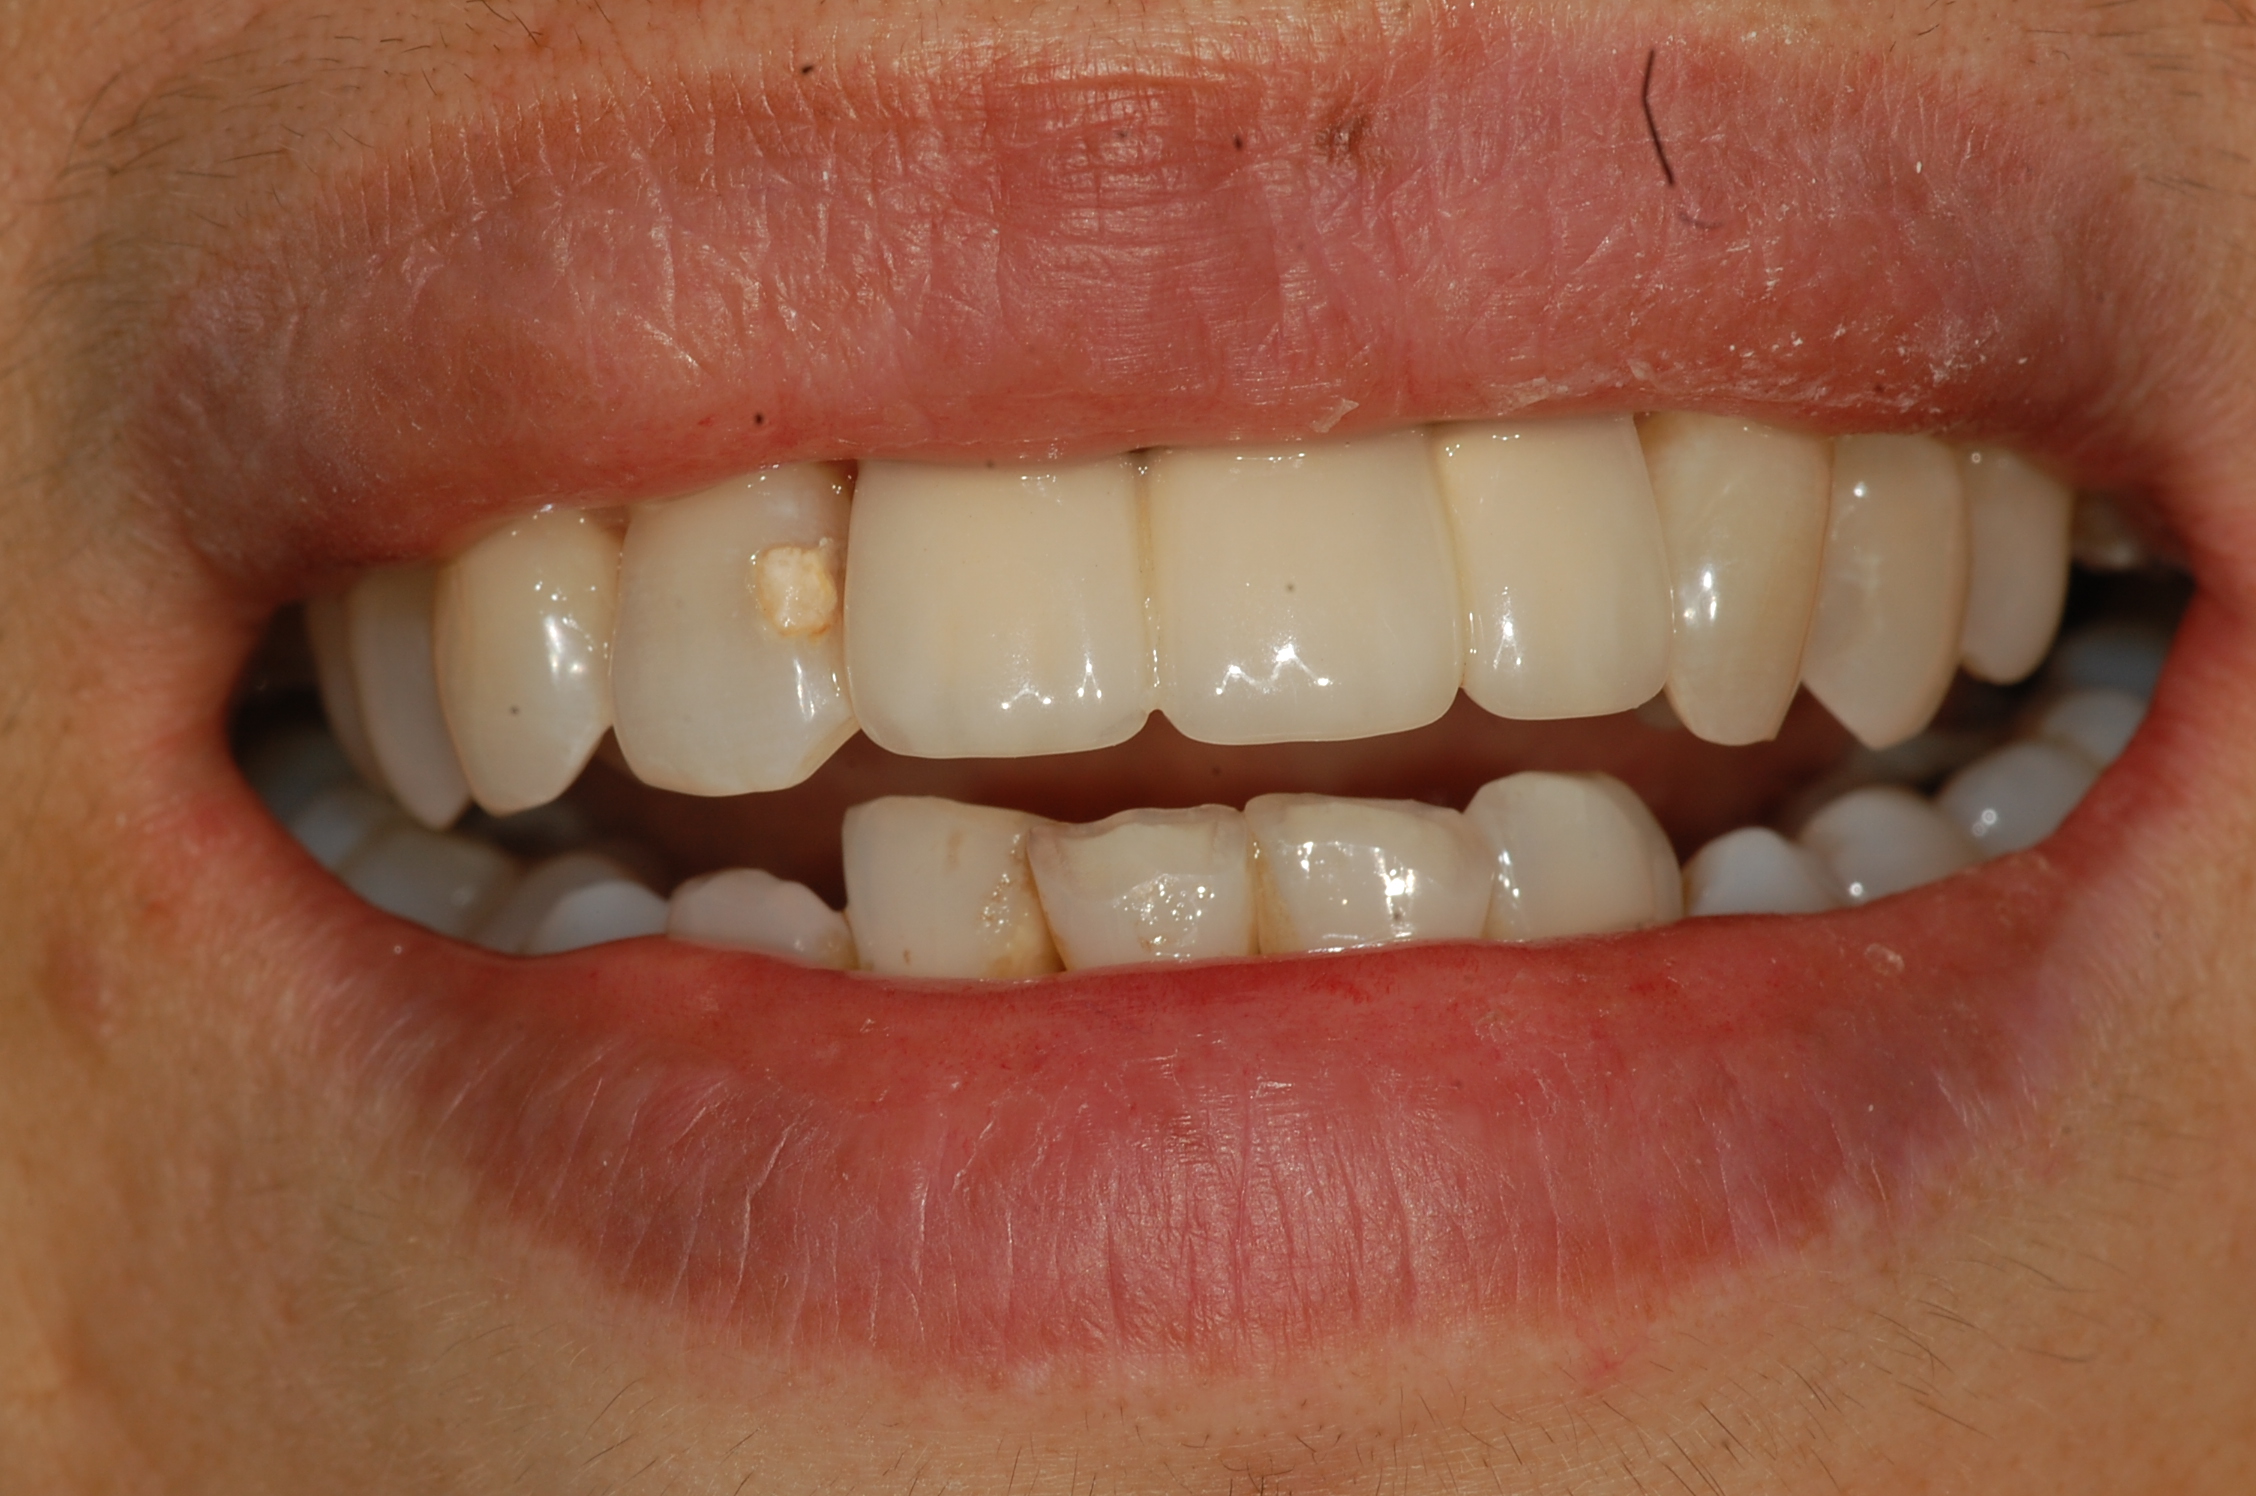

[임플란트] 제목 : 전치부 임플란트 브릿지

앞니의 임플란트입니다.